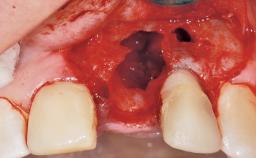

Late Placement of an Implant in a Maxillary Left Central Incisor Site

A 30-year-old female patient had lost tooth 21 and was referred to our clinic for consultation and treatment. Due to advanced apical infection, tooth 21 had been extracted two months earlier at another clinic and an acrylic-resin tooth had been bonded to the adjacent teeth. The patient desired implant treatment to avoid any damage to the adjacent natural teeth. While the patient had no history of any systemic disorder, she was a heavy smoker and exhibited medium to advanced periodontitis in the entire jaw. After the initial treatment to achieve a pocket probing depth of less than 4 mm and no bleeding on probing, a decrease in the height of the papillae mesial and distal to the extraction site and overall gingival recession were observed.

Bone Augmentation Horizontal|Staged

Augmentation Materials Autogenous chips|Membrane

Soft Tissue Grafting Simultaneous